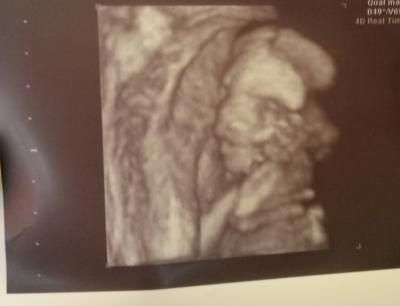

Also alles zeitgerecht entwickelt und unsere maus ist 17-18 cm lang und 200 gramm schwer. Anbei ein 4d bild, bei dem man meiner meinung nach eine Gesichtshälfte ganz gut erkennen kann :)

Das ist ja schön und tolles Foto !!!!!

Oh wie schön! Und ein hübsches Bildchen :-D